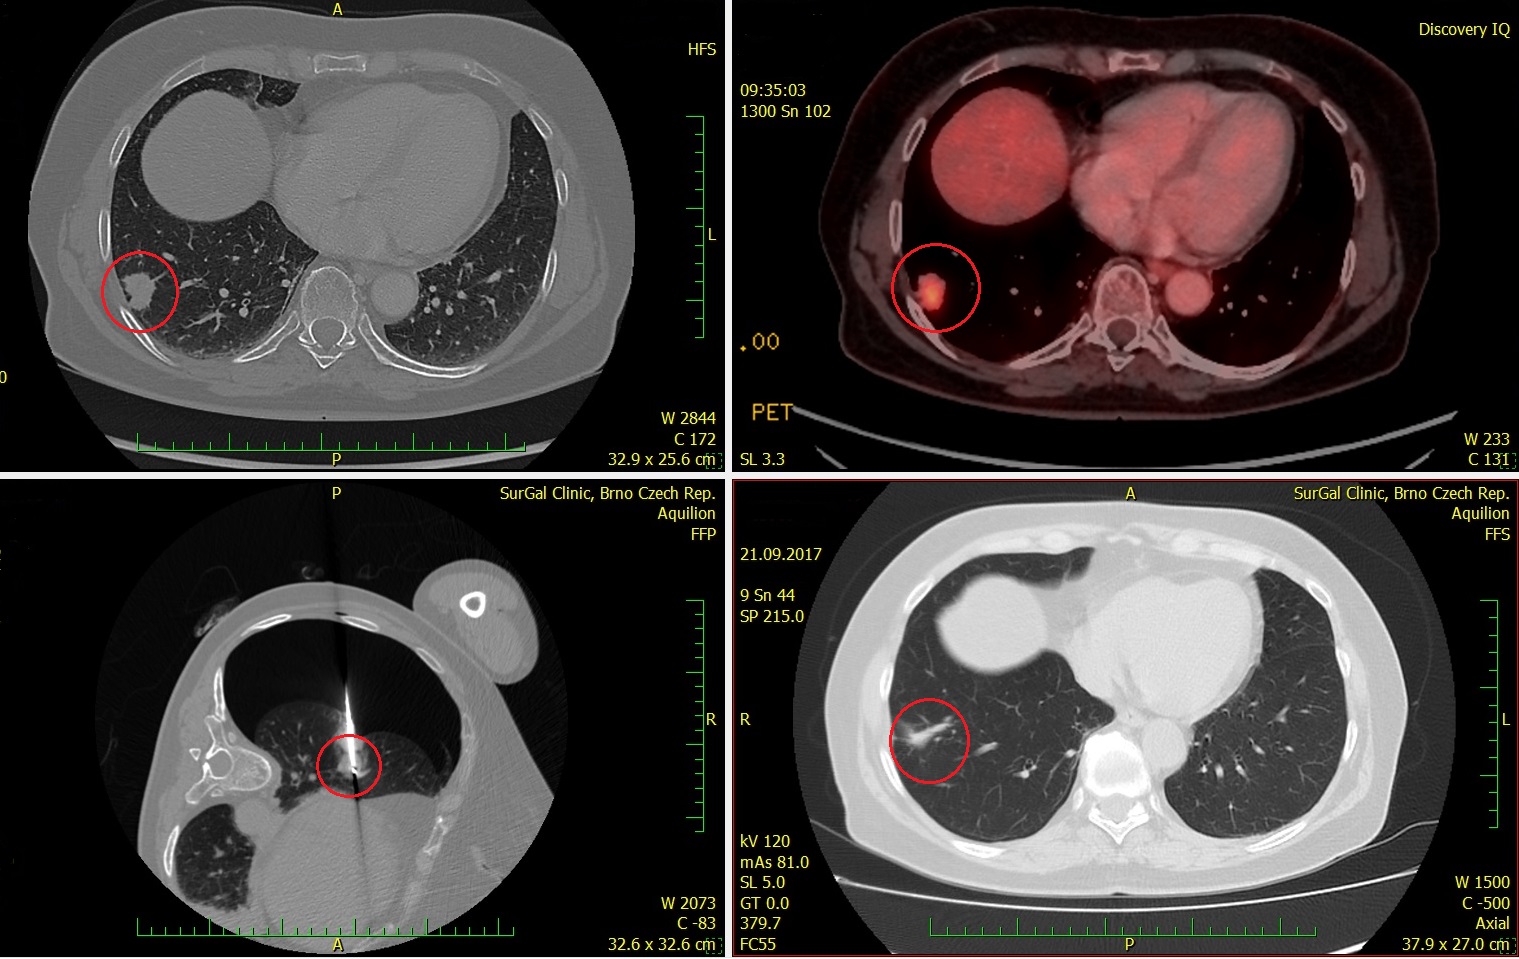

Zákrok byl proveden v červenci 2017, proběhl bez podstatných komplikací, na kontrolním vyšetření v září 2017 je patrné kompletní vymizení ošetřených ložisek primárního nádoru i metastázy (viz CT nález) a pacient je schopen normálního života. Péči hradí zdravotní pojišťovna.

- 3/2017 CT a PET

- 21.9.2017 kontrolní CT, SurGal Clinic, další CT plánováno na 12/2017